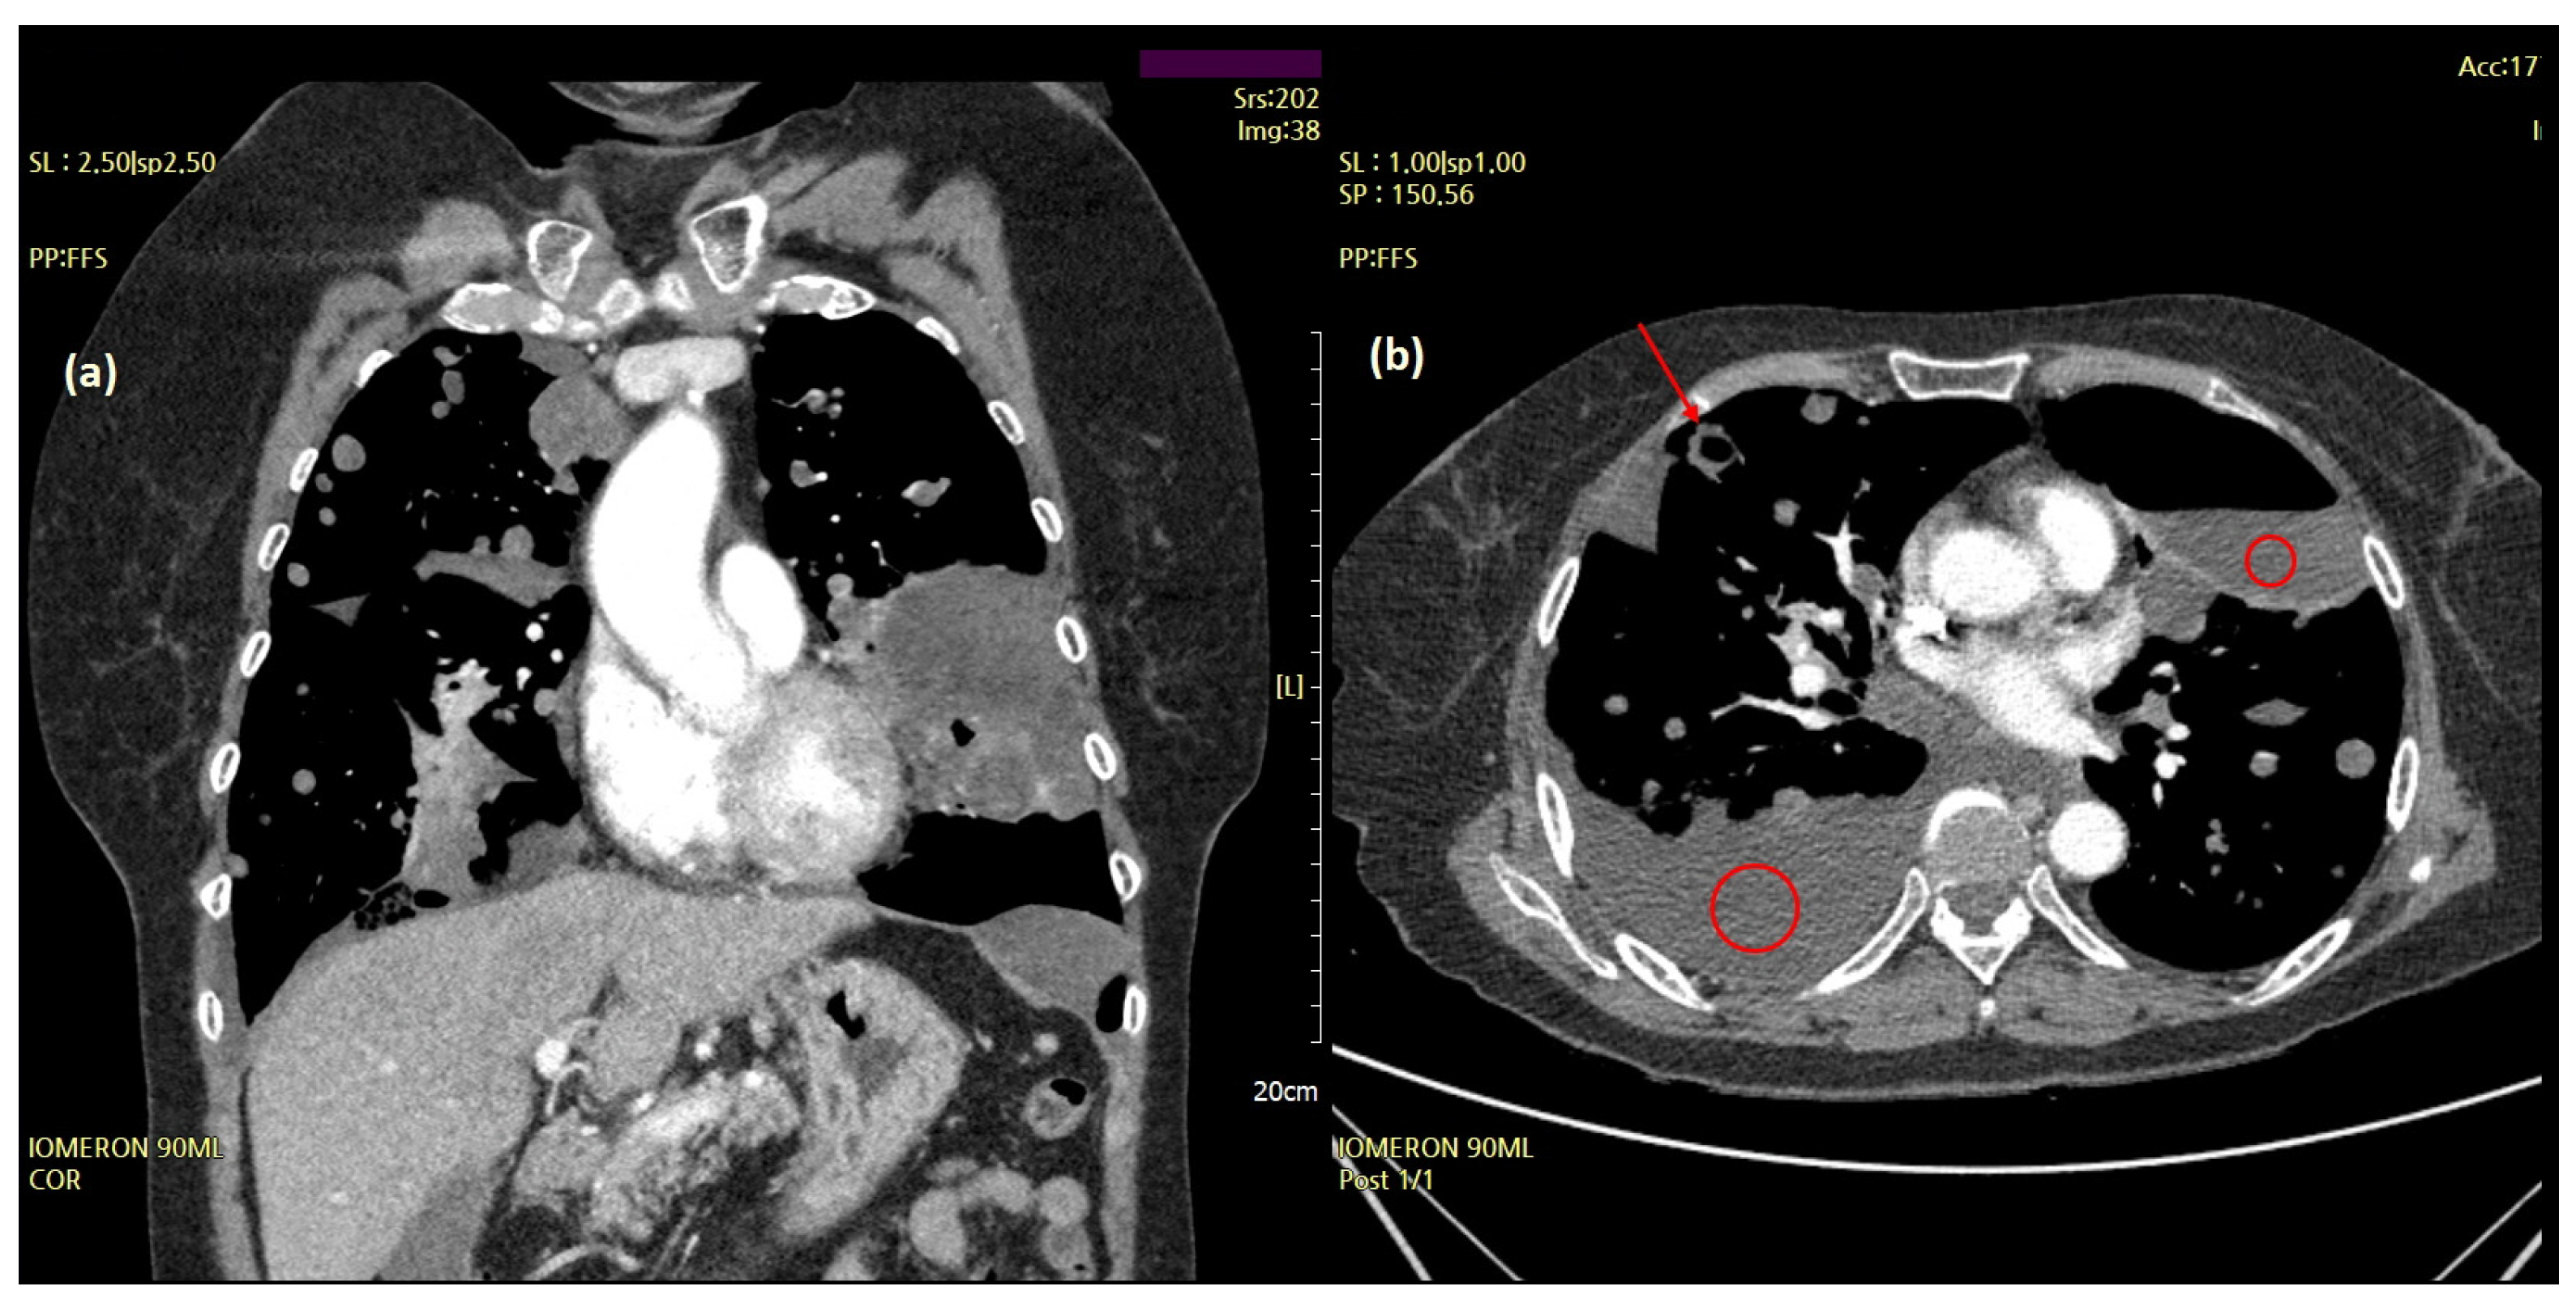

A 70-year-old woman visited the clinic complaining of acute cough and dyspnea in April 2017. A chest X-ray and chest computed tomography (CT) revealed pneumothorax in the left chest and multiple nodules in both the lungs (Figure 1).

Figure 1.

A chest computed tomography (CT) features of the lung masses. A chest CT (April 2017) showed pneumothorax in the left lung and multiple masses in both lungs. The amount of pneumothorax was small (solid arrows) because CT was performed after the chest tube (dotted arrows) was inserted and stabilized.